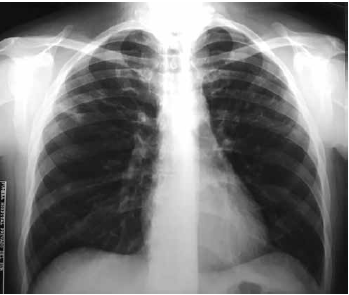

La radiografía de tórax presentaba un patrón intersticial bilateral (Figura 2).